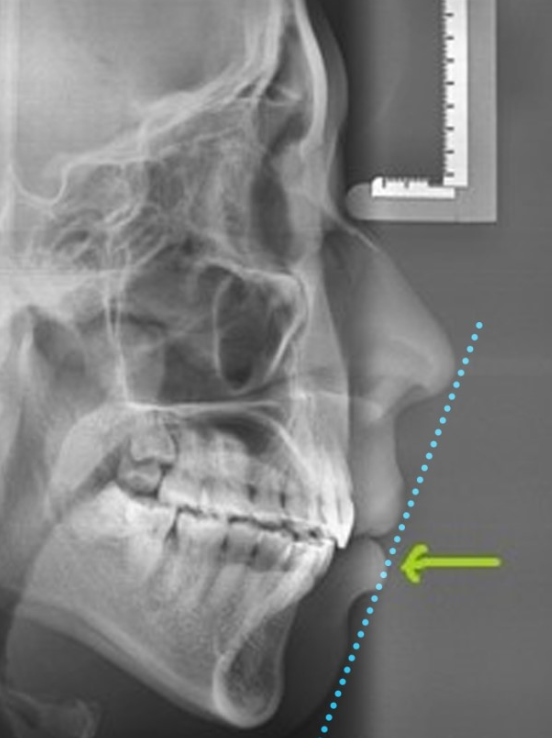

전형적인 한국인 치아 돌출입 증례

위와 같은 경우 투명교정만으로 치아교정이 가능할까요?

결론적으로 가능합니다.

그러나

돌출 정도에 따라 치료 계획도 많이 다르고 기간, 난이도도 많이 다르기 정확한 교정 검진을 통해서 교정기 선택을 하는 것이 무엇보다 중요하다고 할 수 있습니다.

위 사진과 같은 한국형 돌출입 경우 돌출입 특성상 치료가 쉽지 않기 때문에 치료방법의 선택이 아주 중요합니다.

돌출입 교정은 심미선을 기준으로 코끝점에서 부터 턱끝점을 이어 보았을 때 윗입술이 1미리 더 나오고 걸리고 아래입술은 1미리 정도 들어가는 것을 원칙으로 하나

이 같은 기준은 골격적인 부분을 고려하지 않고 코와 턱에 따라 많이 달라지기 때문에 부과적으로 뷰티라인 컨셉을 사용해서 최대한 돌출입 개선과 함께 팔자 주름 같은 부작용을 최소한 하는 것을 목표로 하고 있습니다.

세라믹치과 뷰티라인 컨셉 코끝에서부터 윗입술 아래입술까지 이어지는 S라인을 최대한 부드럽게 표현하는 것을 목표로 합니다.